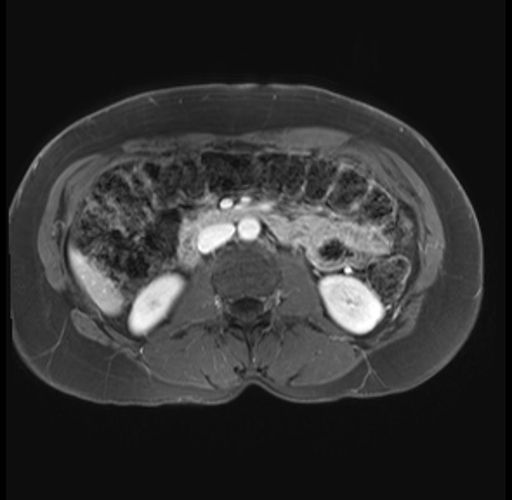

Imaging Analysis

Look through the patient's CT scan to identify any areas of concern for the necessary procedure.

Based on your CT findings, which issue(s) are present and would give reason for "planned slowing down moment(s)" in this case?

Considering a standard distal pancreatectomy procedure, what step(s) of the operation would you do differently in this case?